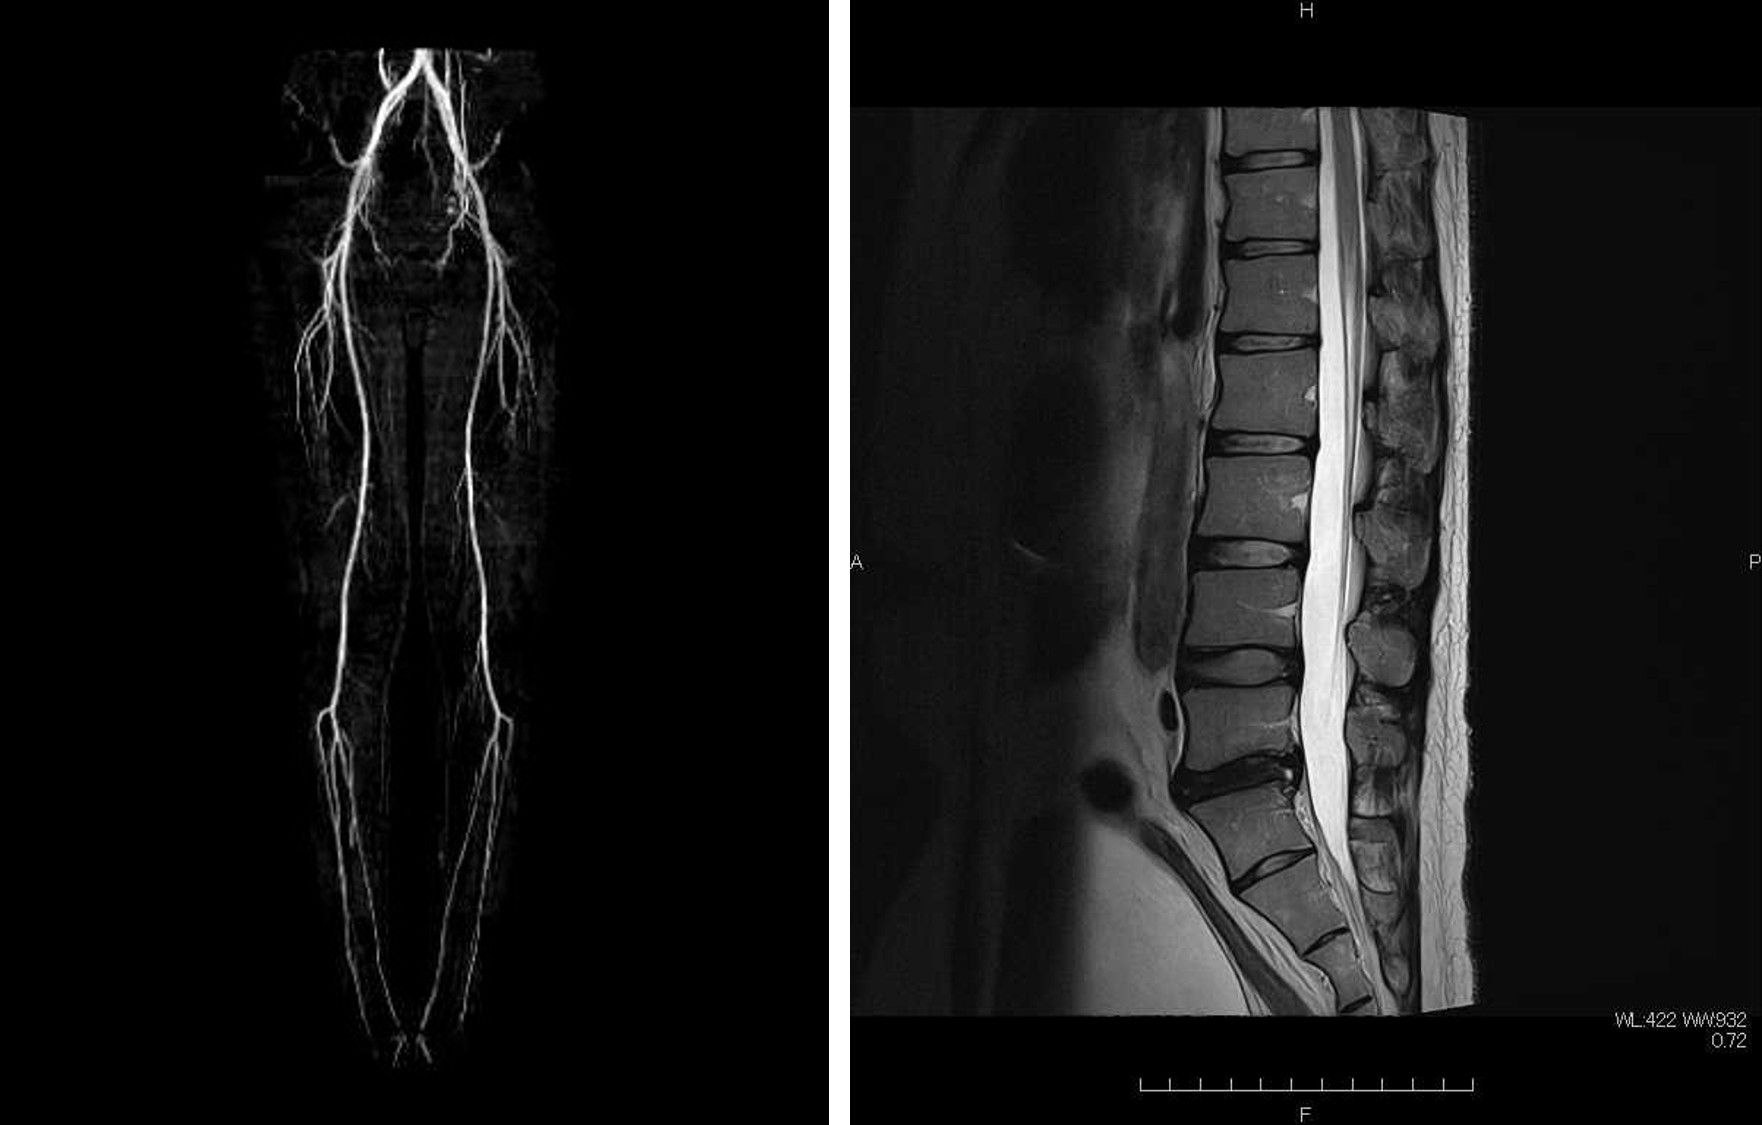

Siemens社製1.5TMRI装置画像

MAGNETOM Alteaにあらたに搭載されたTurbo SuiteとDeep Resolveを組み合わせることで、画質を向上しつつ、ルーチン検査の時間短縮が可能となりました。

2025年6月、Siemens社製MRI1.5T装置「MAGNETOM Altea」が稼働いたしました。

• 「高速撮像の実現」と「AIを用いた画像再構成技術」